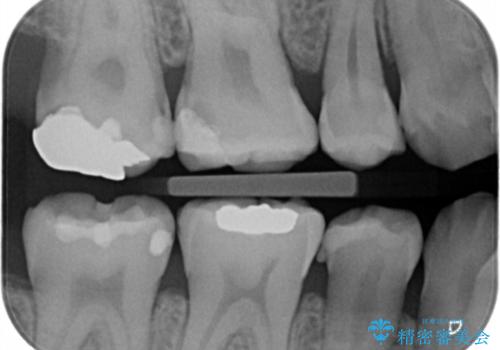

- 一番奥の銀の詰め物を白くしたいとのことで来院。

セラミックの詰め物のやりかえだと範囲が多く、割れてしまうリスクがあります。

そのため、割れるリスクが少ない詰め物ではなく、被せ物による治療(ジルコニアクラウン)を行いました。

また、隣の歯も白い樹脂の下が虫歯になっており、セラミックの詰め物(e-maxインレー)による修復をしました。